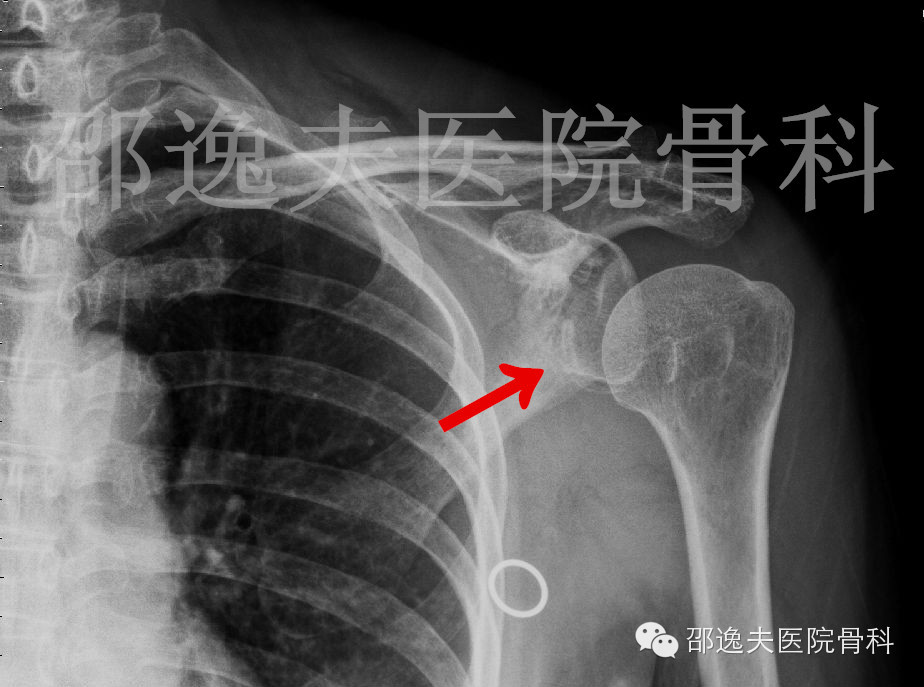

手法复位后X线片

这是典型的骨性Bankart损伤,即指外伤导致肩关节前脱位后与肩关节盂前下缘撞击发生的关节盂前缘撕脱骨折。